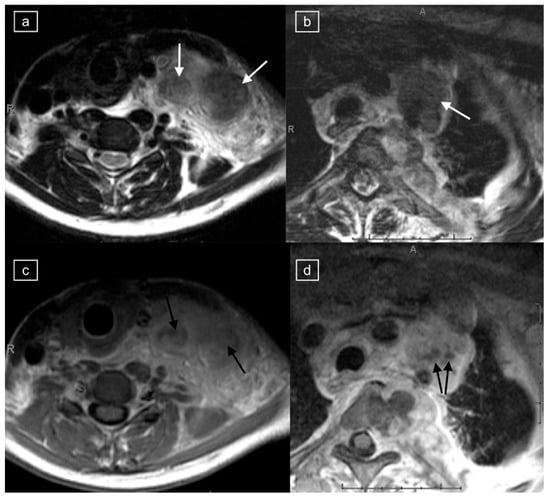

Figure 3.

Images demonstrating technical reasons for lower T2 signal of lymphadenopathy. MRI of the neck and superior mediastinum on coronal T2 with (a) a repetition time (TR) of 4830 and (b) a TR of 5720 [fat-suppressed sequence] in a 14-year-old male with a histologic diagnosis of nodular sclerosing Hodgkin lymphoma. The left cervical and mediastinal lymphadenopathy (straight arrows) show significantly lower signal with lower TR images (a), but even on the higher TR images, central foci within the pathological lymph nodes demonstrate low signal (curved arrows).